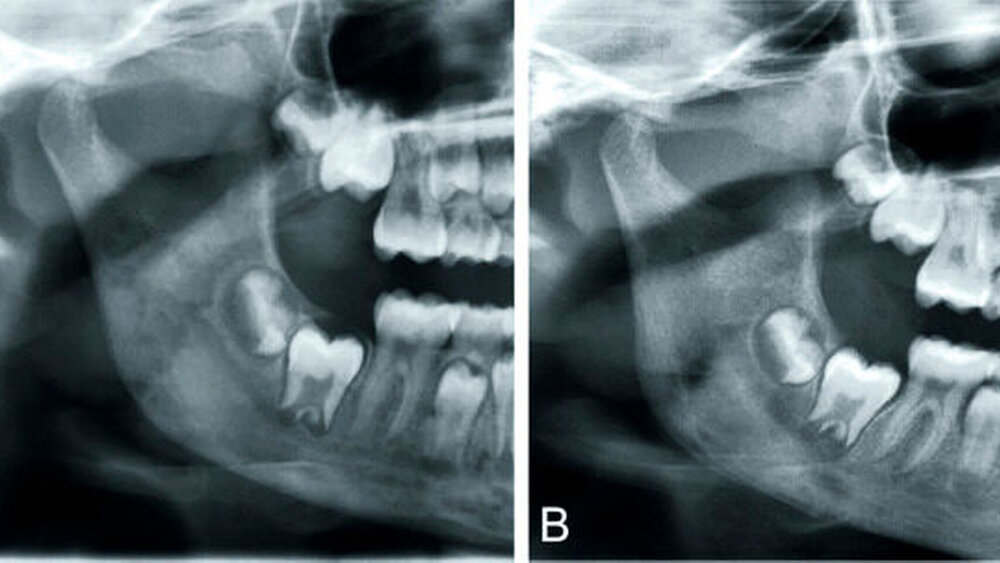

Die primär chronische OM hingegen beginnt ohne eine initiale Akutphase und ist in Ätiologie, Therapie und Prognose als eigenständiges Krankheitsbild zu verstehen (Tabelle, Abbildungen 3, 4, 7).

Primär chronische OM: Zur Behandlung der primär chronischen OM, somit auch der CRMO (Abbildungen 3 und 4) und des SAPHO-Syndroms (Abbildung 7), haben sich nicht steroidale Antiphlogistika (NSAR) und Kortikoide bewährt, bei Therapieresistenz Methotrexat (MTX), Bisphosphonate wie Pamidronat [Urade et al., 2012; Kuijpers et al., 2011] und TNF-alpha-Antagonisten wie Infliximab [Costa-Reis et al., 2013]. Adjuvant können Antibiotika, die hyperbare Sauerstofftherapie HBO und Calcitonin hilfreich sein. Auch bei dieser Form ist eine Gewebeprobe aus oben genannten Gründen stets anzustreben. Ein mikrobieller Abstrich ist zur Differenzialdiagnostik prinzipiell sinnvoll, häufig jedoch bei fehlender Abszessbildung beziehungsweise Kontamination durch die orale Flora nicht zielführend. Auffällig ist, dass es keine pauschale Therapieempfehlung gibt. Mitunter sind mehrere Therapieoptionen zu über-prüfen und letztendlich die anzuwenden, auf die der Patient am besten anspricht.